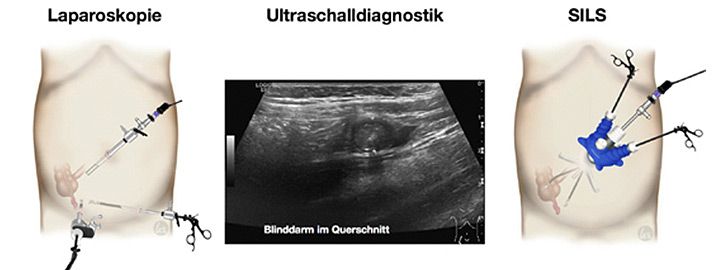

Die Diagnose der Appendizitis wird durch die ärztliche Untersuchung gestellt, allerdings ergänzt durch Ultraschall-, Blut- und Urinuntersuchungen.

Unbehandelt kann die Entzündung bis zum Durchbruch (Perforation in die freie Bauchhöhle) führen. Wir empfehlen die operative Blinddarmentfernung (Appendektomie), die in unserer Klinik minimal invasiv durchgeführt wird verbunden mit zahlreichen Vorteilen dieser Methode.